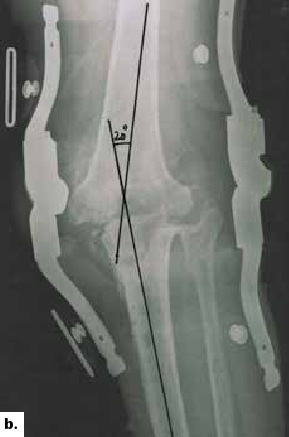

Als Osteosynthesematerial dient ein Fixateur externe, der sich auf die beiden knienahen Drittel erstreckt (Abb. 2a u. b). Der Durchbau dauert bis zu einem Jahr. Nach 3 bis 4 Monaten kann der Fixateur durch eine hintere Schalenorthese mit beweglicher Sandale ersetzt werden. Damit lassen sich die ersten Schritte unternehmen. Nachträglich lassen sich die beiden Knochenstümpfe durch eine Arthrodese mit einem Marknagel stabilisieren 5.